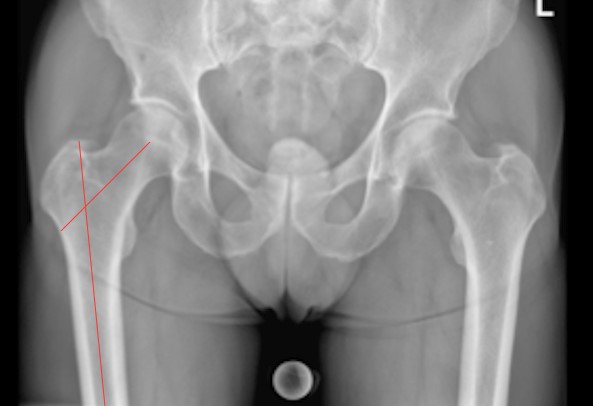

Bild: Lehrbuch Orthopädie. Was man wissen muss. Prof. Dr. Mazda Farshad. Springer 2021 © CC BY-NC 4.0

Die typischen Untersuchungsbefunde sind die stark verminderte Innendrehung der Hüfte und der positive Impingement-Test, das heisst das Auslösen der bekannten Schmerzen bei endgradiger Innendrehung in gebeugter Position der Hüfte.

Da der Impingement-Test auch bei anderen Hüfterkrankungen positiv ausfallen kann, ist eine fachärztliche Untersuchung erforderlich, um die korrekte Diagnose zu stellen und Differentialdiagnosen auszuschliessen. Die klinische Untersuchung wird ergänzt durch konventionelle Röntgenbilder, auf denen die klassischen Impingement-Merkmale gut sichtbar sind. Durch ihre sehr hohe Aussagekraft lässt sich die Diagnose bereits bestätigen. Zudem kann bereits eine Aussage zur führenden Komponente der Formstörung und allenfalls zu bereits vorhandenen Folgeerscheinungen gemacht werden.